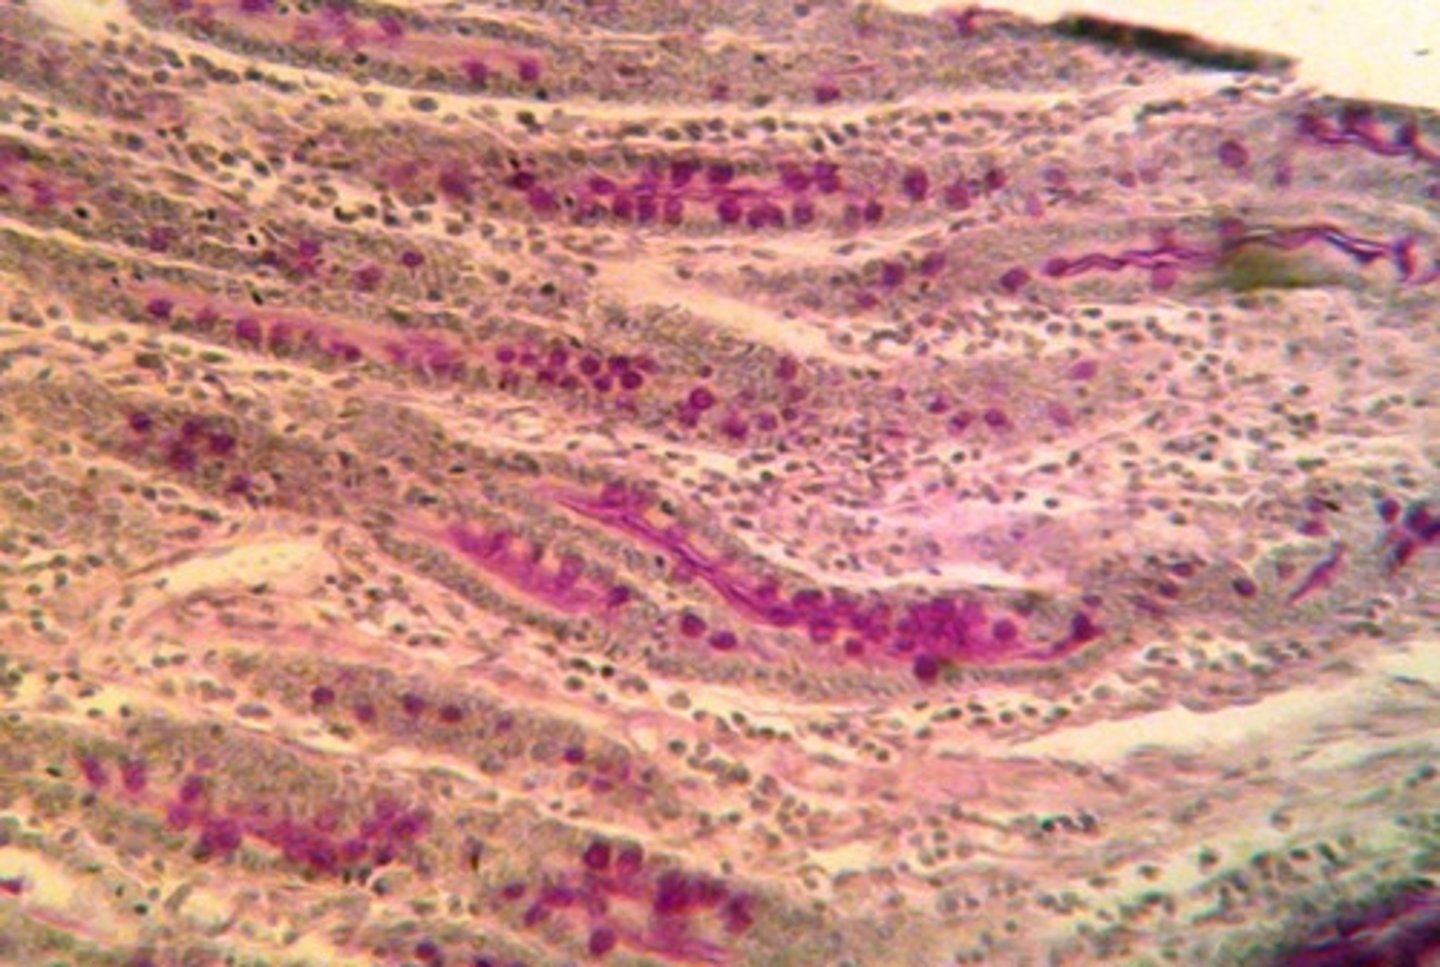

What is the Volcano Lesion in C. diff pathology?

A histological feature of Pseudomembranous Colitis with a fountain of fibrin, mucus, and neutrophils.

How do you identify Intestinal Metaplasia (Barrett's Oesophagus)?

Use Alcian Blue to look for Goblet cells (bright blue circles) in a tissue where they don't belong (like the oesophagus or stomach).